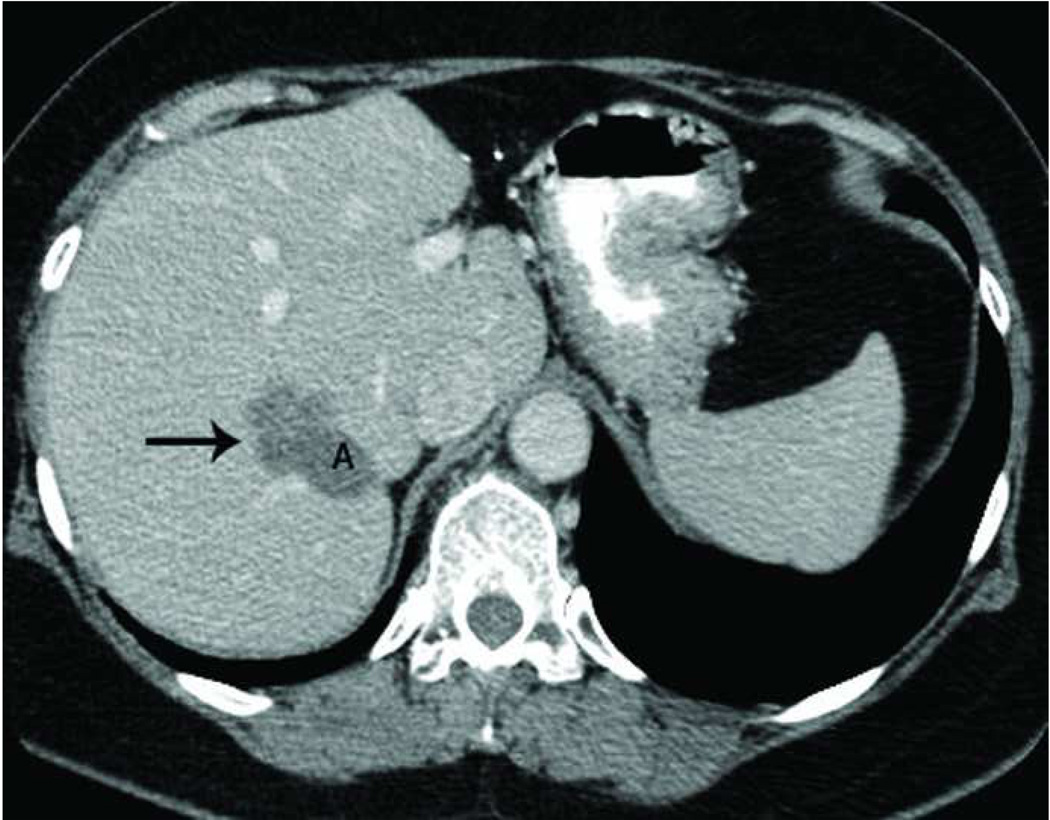

The liver is a vascular solid organ with an abundance of large vessels creating the potential for heat sink effects (Figure 5). Microwaves appear to be more apt to overcome perfusion and large heat sinks than other heat based ablation modalities (5, 10, 48–50). Microwave energy has been shown to ablate tissue up to and around large hepatic vessels measuring up to 10 mm and creates larger zones of ablation in high perfusion areas (5, 49–50). High perfusion rates in hepatic vessels greater than 3 mm limits the effectiveness of radiofrequency ablation, and has been shown to be an independent predictor of incomplete tumor destruction (51).

Figure 5.

Recurrence along a hepatic vein following RF ablation. Pretreatment CT image (a) demonstrates a small low attenuation lesion located between hepatic venous branches (arrow) concerning for metastatic disease in this patient with colorectal cancer. US image during treatment with RF ablation (b) demonstrates gas encompassing the small lesion. Follow up CT (c) demonstrates a low attenuation ablation zone (A) with local tumor progression along the margin abutting the hepatic vein (arrow).